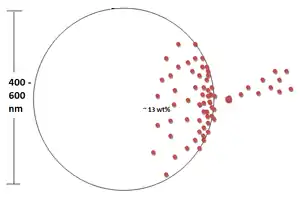

Dexamethasone (DEX) is a glucocorticoid that is used as an anti-inflammatory and immunosuppressive agent. PLGA nanoparticles loaded with DEX via oil-in-water emulsion/solvent evaporation method can be embedded in alginate hydrogel matrices. To quantify the amount of DEX that was successfully seeding into the nanoparticle, UV spectrophotometry can be used. It has been shown that the amount of DEX that can be successfully loaded into the nanoparticles was ≈13 wt% and the typical particle size ranged from 400 to 600 nm.

In vitro tests have revealed that the impedance of the nanoparticle-loaded hydrogel-coated electrodes have similar impedance to the non-coated electrode (bare gold). This shows that the nanoparticle-loaded hydrogel coating does not significantly hinder the electrical transport. The in vivo tests have shown that the impedance amplitude of the DEX-loaded electrodes was maintained at the same level it was at initially. However, non-coated electrodes had an impedance about 3 times greater than its original impedance 2 weeks earlier. This addition of anti-inflammatory drugs via nanoparticles indicates that this form of surface modification does not have a negative effect on the electrodes performance.[14]